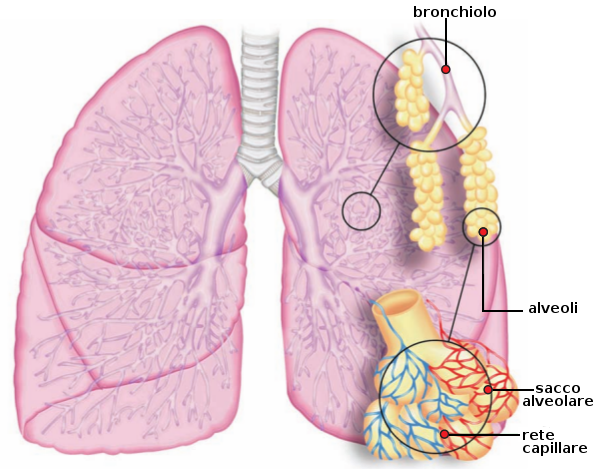

- Polmoni: Sono due organi spugnosi, elastici e rosei, che sono alloggiati nella cavità toracica. Sono appoggiati sul muscolo diaframmatico e protetti da una membrana - che li avvolge - chiamata pleura. Questa presenta due foglietti: la pleura viscerale adesa al polmone e la pleura parietale adesa alla parete toracica. Questi due foglietti scivolano uno sopra l'altro durante i movimenti respiratori. Tra i due foglietti si trova la cavità pleurica, dove si trova una piccola quantità di liquido, che agisce come lubrificante. L'elasticità della pleura le permette di accompagnare i movimenti della gabbia toracica durante la meccanica respiratoria.

- Bronchi: La trachea si biforca in due condotti, i bronchi, in una zona chiamata carena. Questi condotti sono formati da una serie di anelli cartilaginei incompleti nei bronchi più grossi e completi nei bronchi più piccoli, che si dirigono verso i polmoni.

Ematosi e respirazione cellulare

L'ematosi consiste nell'interscambio gassoso tra il sangue e l'aria alveolare. I capillari sanguigni (ramificazioni delle arterie polmonari) giungono agli alveoli polmonari con sangue carbossigenato. I gas attraversano gli epiteli polmonari e i capillari per diffusione passiva, ovvero passano dal luogo a maggior concentrazione a quello a minore concentrazione: